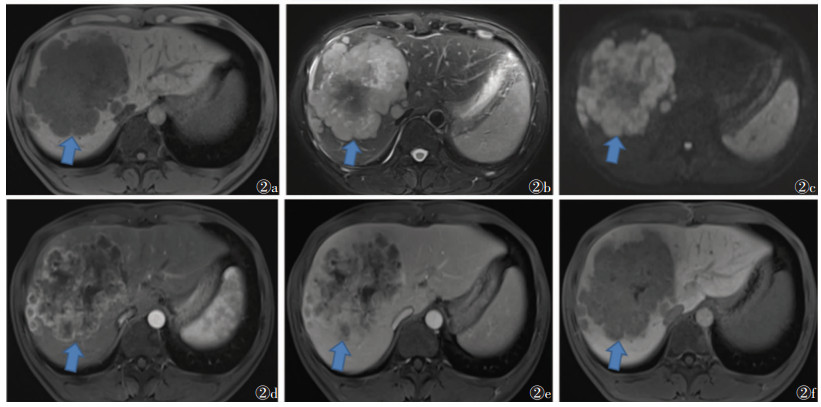

2 结果2组术前MRI表现见表 1,2组发病部位、强化模式、包膜、肝内胆管扩张、淋巴结转移方面比较,差异均有统计学意义(均P<0.05);2组肿瘤数量、最大径、信号特点、脉管瘤栓、肝内转移、肝硬化、门脉高压、腹水例数比较,差异均无统计学意义(均P > 0.05)。见图 1,2。

| 图 2 男,35岁,ICC,AFP值1.92 μg/L 图2a 轴位T1WI示病灶位于肝右叶,呈多发团块状,信号尚均匀,呈低信号 图2b 轴位T2WI脂肪抑制序列呈高信号,信号不均;较大者11.0cm×9.3 cm,边缘模糊,形态欠规则 图2c DWI上病灶呈稍高信号 图2d 增强扫描动脉期病灶呈明显不均匀强化 图2e,2f 分别为门脉期、延迟期,病灶呈相对低信号,周边见环形强化影,强化方式表现为快进快出(箭头) |